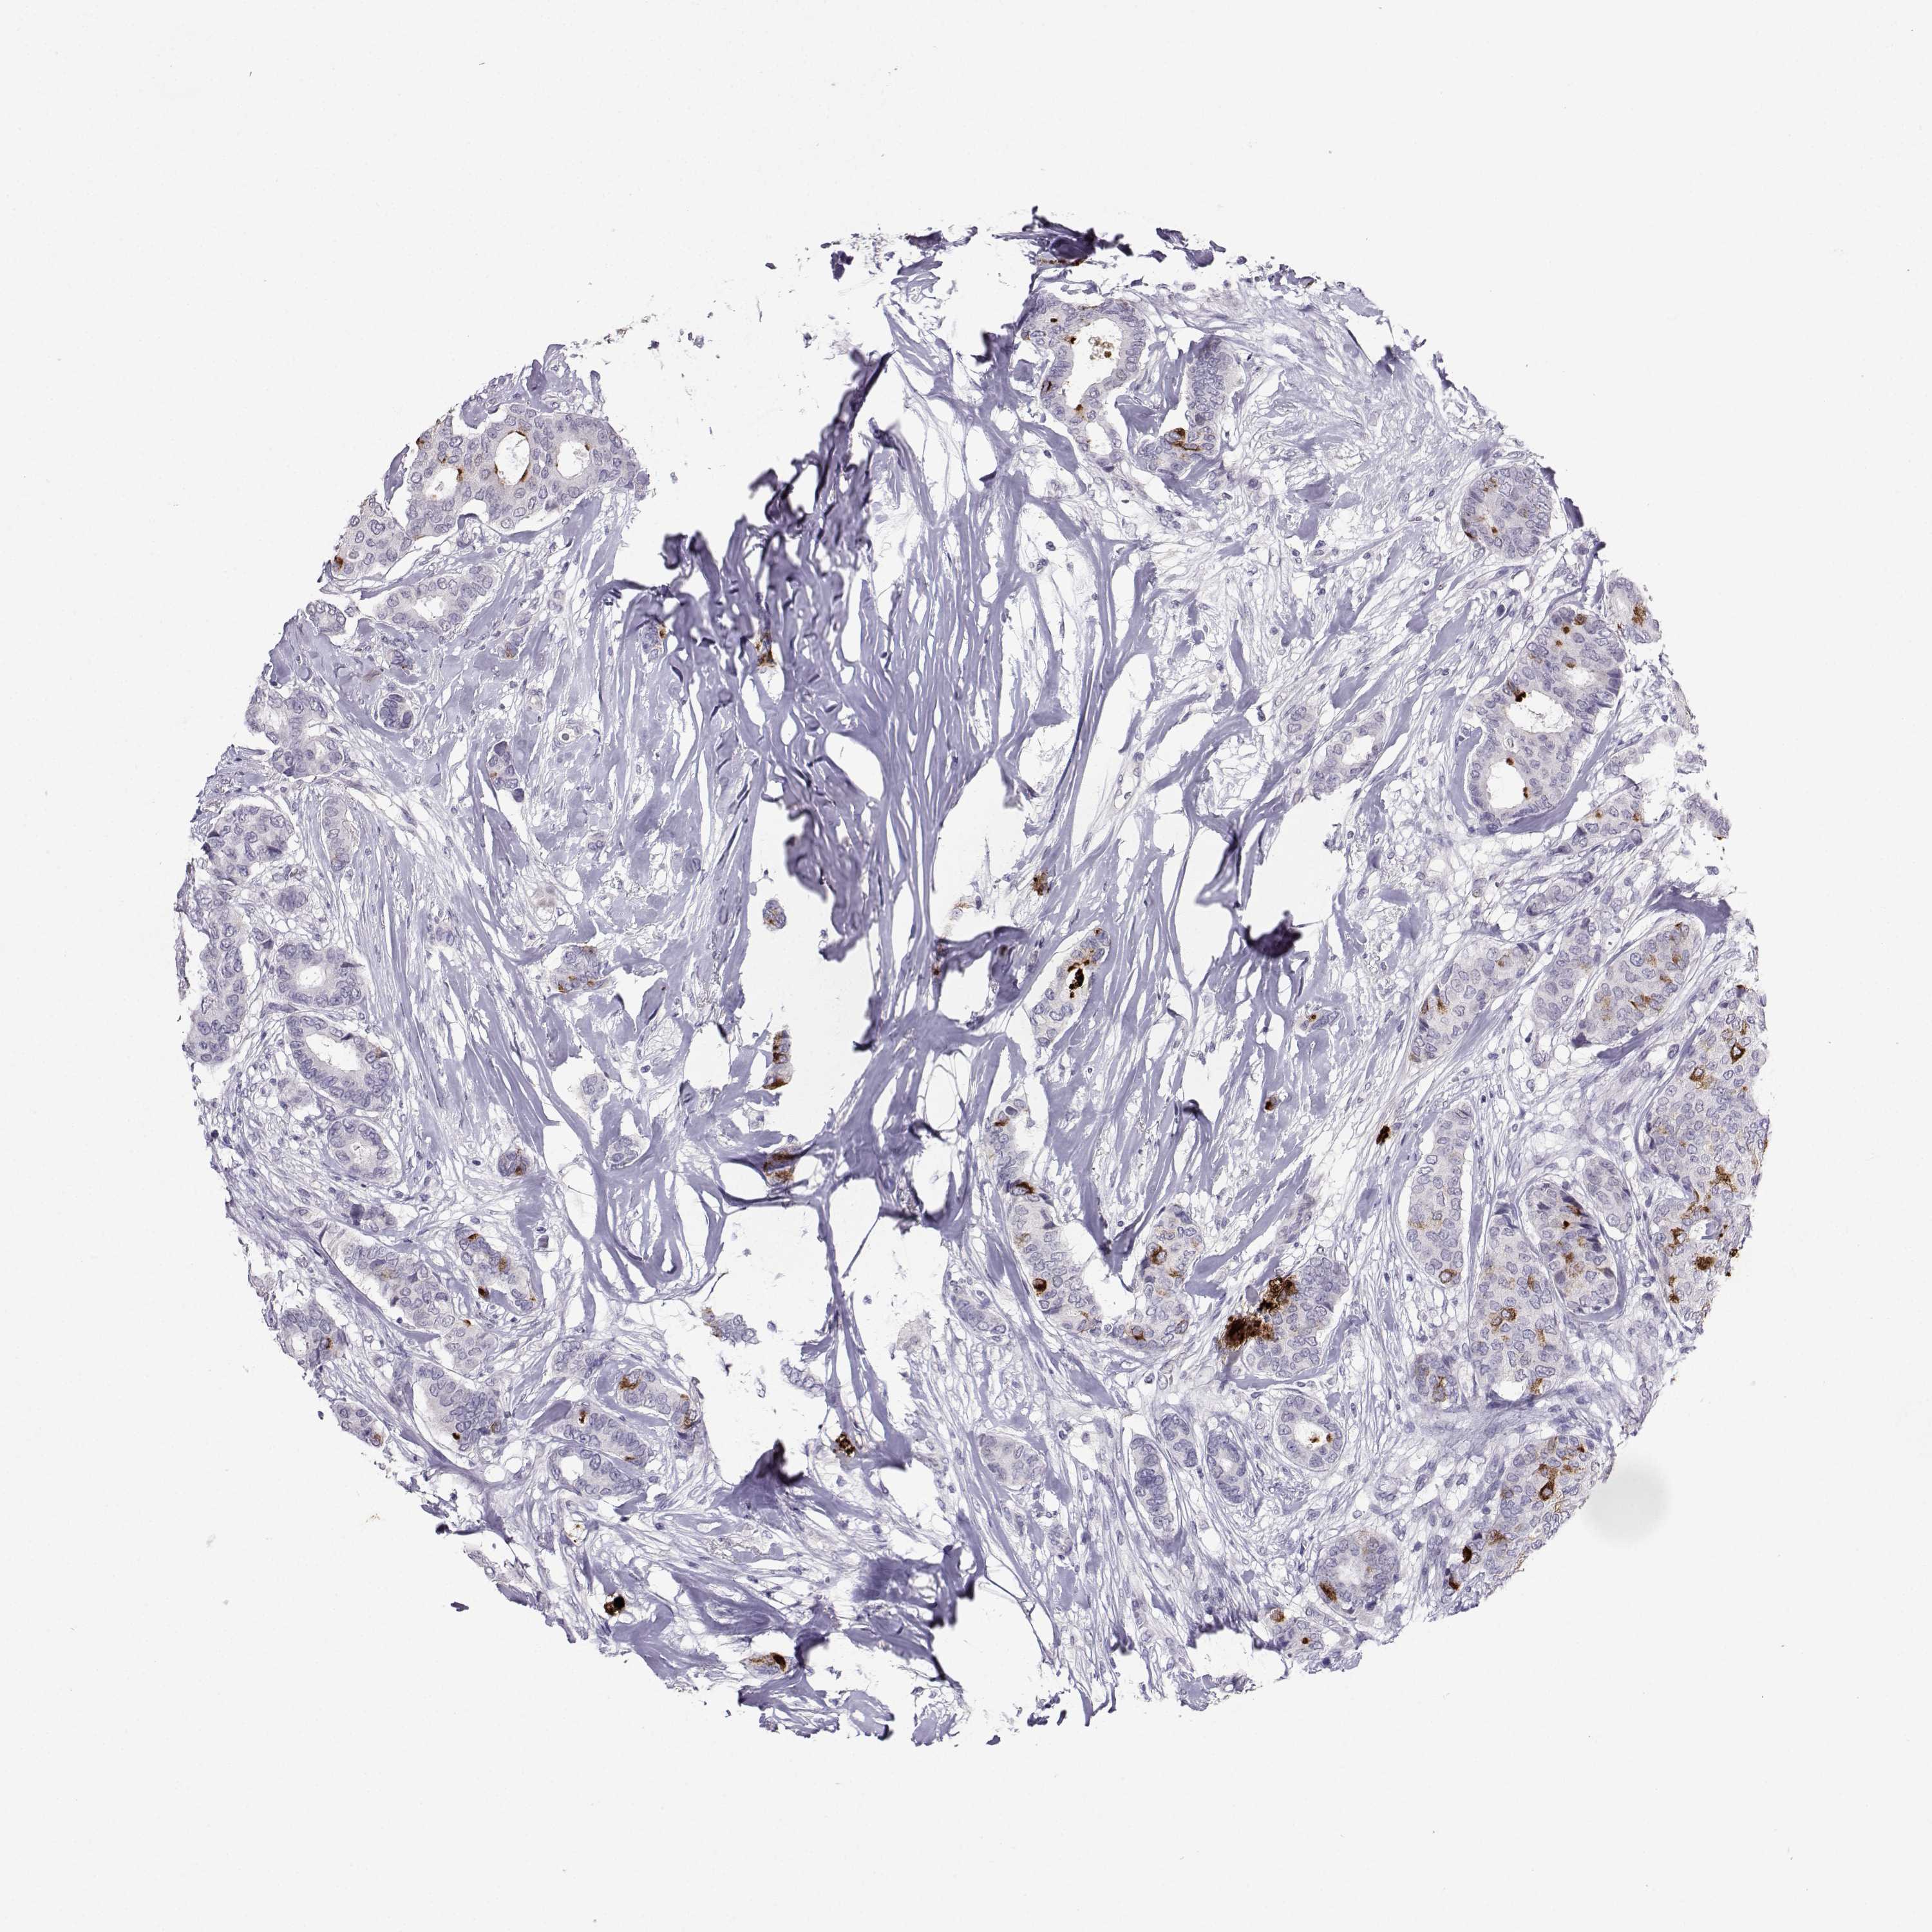

BRCA TCGA BRCA VALIDATION PROTEIN EXPRESSION

ANTIBODIES

AND

VALIDATION

Breast cancer

Human cancer